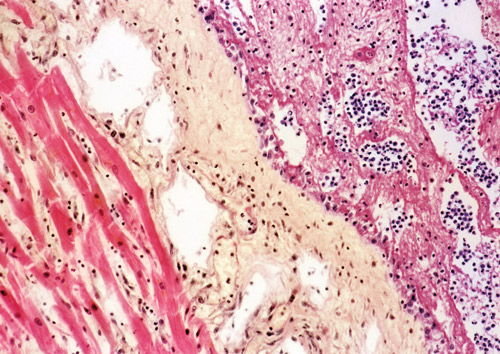

120 pasienter ved fire italienske sykehus med første residiv etter akutt perikarditt ble randomisert til å få kolkisin eller placebo i tillegg til konvensjonell behandling med antiinflammatoriske legemidler (1). Startdosen var 1 – 2 mg første dag, deretter 0,5 – 1,0 mg per dag i seks måneder.

Innen 18 måneder fikk henholdsvis 24 % og 55 % nytt utbrudd av perikarditt (relativ risikoreduksjon 0,56; 95 % KI 0,27 – 0,73). Dessuten reduserte kolkisin symptomvarigheten og antall residiver og økte tiden til første residiv. Forekomsten av bivirkninger var omtrent like stor i begge gruppene. Kolkisin og placebo ble seponert like ofte, mest pga. gastrointestinale plager.

– Denne studien dokumenterer en positiv effekt av kolkisin ved perikarditt, sier professor Rune Wiseth ved Hjerteavdelingen, St. Olavs hospital. – Kolkisin er ikke godkjent for forebygging av perikarditt, verken i Europa eller USA, men er nevnt i europeiske retningslinjer fra 2004. I Norge er preparatet ikke tatt med i Felleskatalogen, men er omtalt i Legemiddelhåndboka. Virkningsmekanismen er uklar, men den er antakelig knyttet til midlets evne til å konsentrere seg i leukocytter, noe som gir hemmet inflammasjon uten toksiske effekter. Bivirkningsrisiko ved lengre tids behandling er fortsatt usikker, sier Wiseth.